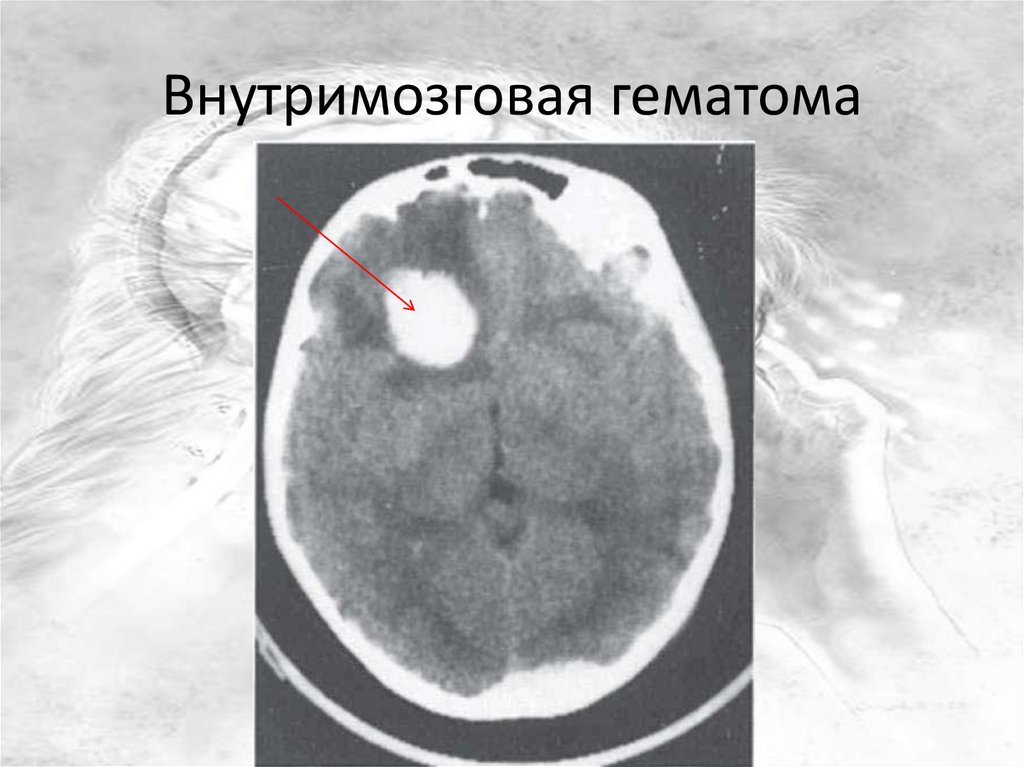

Внутримозговая гематома